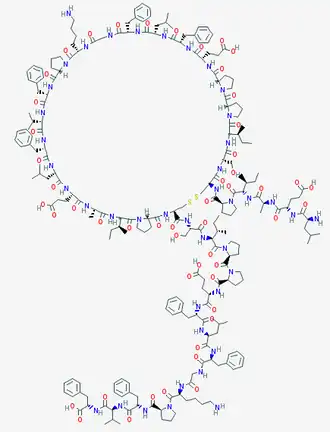

The VIR-576 is a peptide.[7] Consequently, it is a molecule formed by a sequence of amino-acids united by peptide bonds. If we compare both primary structures, it can be seen that the VIR-576 has 2 subunits. Each subunit, monomer is a variant form, a mutant of the VIRIP,[1] differing from four amino acids.

Thus, among the new ones introduced, it is important to emphasize the importance of the cysteine (C) introduced replacing the methionine (M), both being sulfated amino acids, in the stabilization of its structure.

VIR-576 can establish more hydrogen bonds because it has 41 H-bond donors and 56 H-bond acceptors[8] in comparison with the 23 H-bond donors and 30 H-bond acceptors[9] of the VIRIP.Therefore, it's able to form more interactions and react with the gp-41 in a higher intensity than the VIRIP.

Another important interaction that we must underline is the disulfide bond established between both cysteines of the two monomers of the VIR-576 which allows the peptide to have more structural stability in the space in comparison with the VIRIP. Moreover, the ring form that appears in the secondary structure is due to this interaction between both sulfate atoms. Thanks to this disulfide bond, a cystine is formed. This fact allows the union of the subunits during the reaction with the gp41 and also allows them to act simultaneously. Thanks to all this activity and to the dimerization respect to the VIRIP, the VIR-576 is more effective.[10]